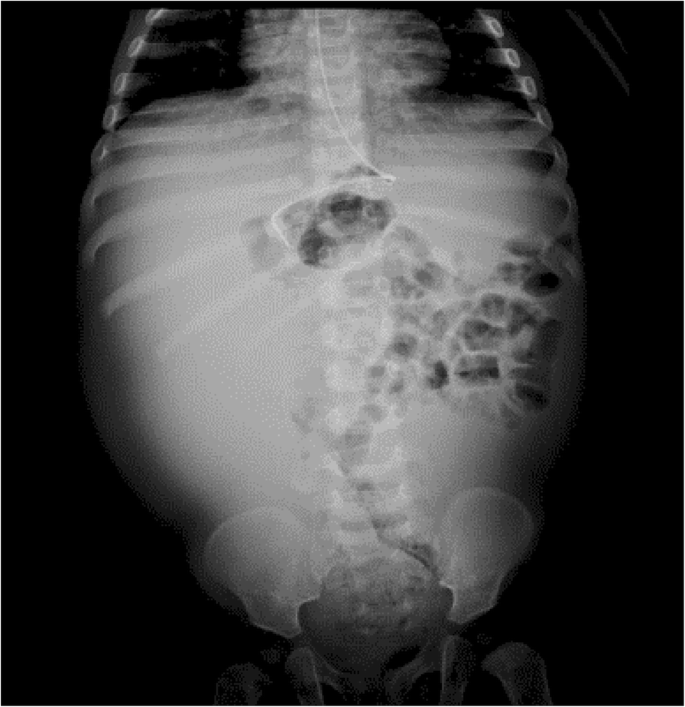

The paraclinical tests showed leukocytosis with neutrophilia and thrombocytosis, high CRP (97.1 mg/dL), mild hyponatremia (Na: 134 mmol/L), potassium, chloride, and calcium within a normal range; normal glycemia; kidney function within normal parameters; and coproscopic exam does not show parasitic structures. Abdominal ultrasound shows a multiseptate image which occupies the right half of the abdomen and displaces the bowel loops and could correspond to septate ascitic fluid; distension of intestinal loops. X-ray of the abdomen where displacement of the bowel loops to the left and opacification of the right half of the abdomen is seen (Fig. 2).

In the case of our patient, abdominal radiography and abdominal ultrasound were performed when an abdominal mass was identified upon palpation, which showed displacement of the intestinal loops to the left and opacification of the right hemiabdomen, and a multiseptate image that occupied the right hemiabdomen and displaced the bowel loops, respectively.